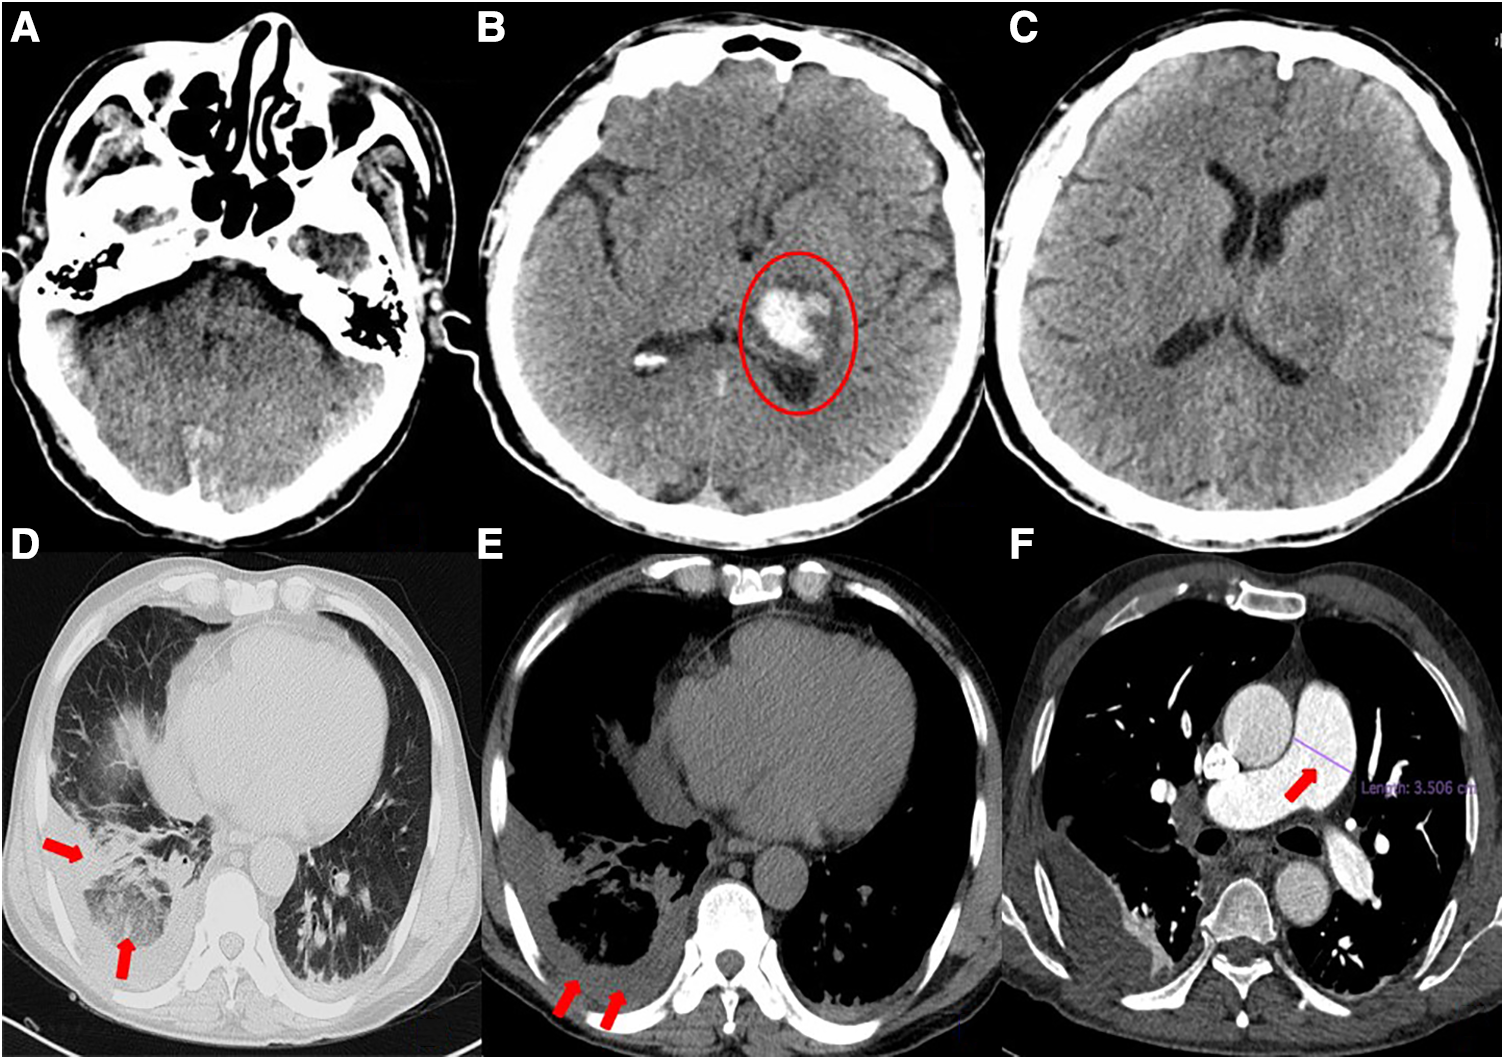

A 54-year-old man was transferred from the local hospital to our hospital's chest pain center in the emergency department due to suspected AMI. The ECG obtained at the local hospital showed ST-segment elevation in the inferior wall leads (II, III, and aVF), indicating possible damage to the heart muscle in that area and a complete atrioventricular block (Figure 1A). When the patient arrived at our emergency department, another ECG was performed, which showed a sinus rhythm with ST-segment elevation in the inferior wall leads (Figure 1B). The patient did not exhibit obvious difficulty in breathing. The laboratory results showed a high percentage of neutrophils (84.3%), indicating an inflammatory response in the body. Furthermore, the results of biomarker analysis were as follows: cardiac troponin-T (cTnT) level, 474.4 ng/L; myoglobin (Mb) level, 565.30 ng/ml; creatine kinase MB (CK-MB) level, 108.00 ng/ml; and brain natriuretic peptide level, 264 pg/ml. Moreover, the patient underwent general cranial computed tomography (CT) scans (Figures 2A–C) and chest CT scans (Figures 2D–F) to assess any further complications or conditions.

Figure 2

(A–C) General cranial computed tomography scan. A 3.3 × 2.3-cm left thalamic hematoma (red circle) is visible, with minimal surrounding edema. There is no evidence of midline shift. (D–F) Chest computed tomography scan. Scattered infection foci in bilateral lungs (especially in the lower lobes of both lungs), thickened bilateral pleura, right lower lobe atelectasis, right pleural effusion, and suspected pulmonary infarction can be seen. The pulmonary artery trunk is enlarged (red arrow).

Six days prior to admission to our hospital, the patient was admitted to the local hospital with symptoms of headache, right limb immobility, unclear speech, nausea, and vomiting. His blood pressure was measured at 180/120 mmHg and a cranial CT scan revealed intracerebral hemorrhage (ICH) in the thalamus. As a result, the patient was diagnosed with ICH. During his hospital stay, he experienced precordial squeezing chest pain, which lasted for approximately 1.5 h. This chest pain was accompanied by diaphoresis, palpitations, dyspnea, nausea, and vomiting. Given the symptoms and ECG changes indicating inferior wall involvement, acute inferior myocardial infarction were suspected.

However, a coagulation function test revealed a D-dimer level of 22.48 mg/L in the patient's blood. During the patient's hospitalization, the presence of hemoptysis and deep vein thrombosis (DVT) in their lower extremity were observed. Based on these symptoms, a possible diagnosis of PE was considered. To confirm this diagnosis, a computed tomography pulmonary angiography (CTPA) was performed (Figures 3D–F), and the diagnosis of PE was confirmed.